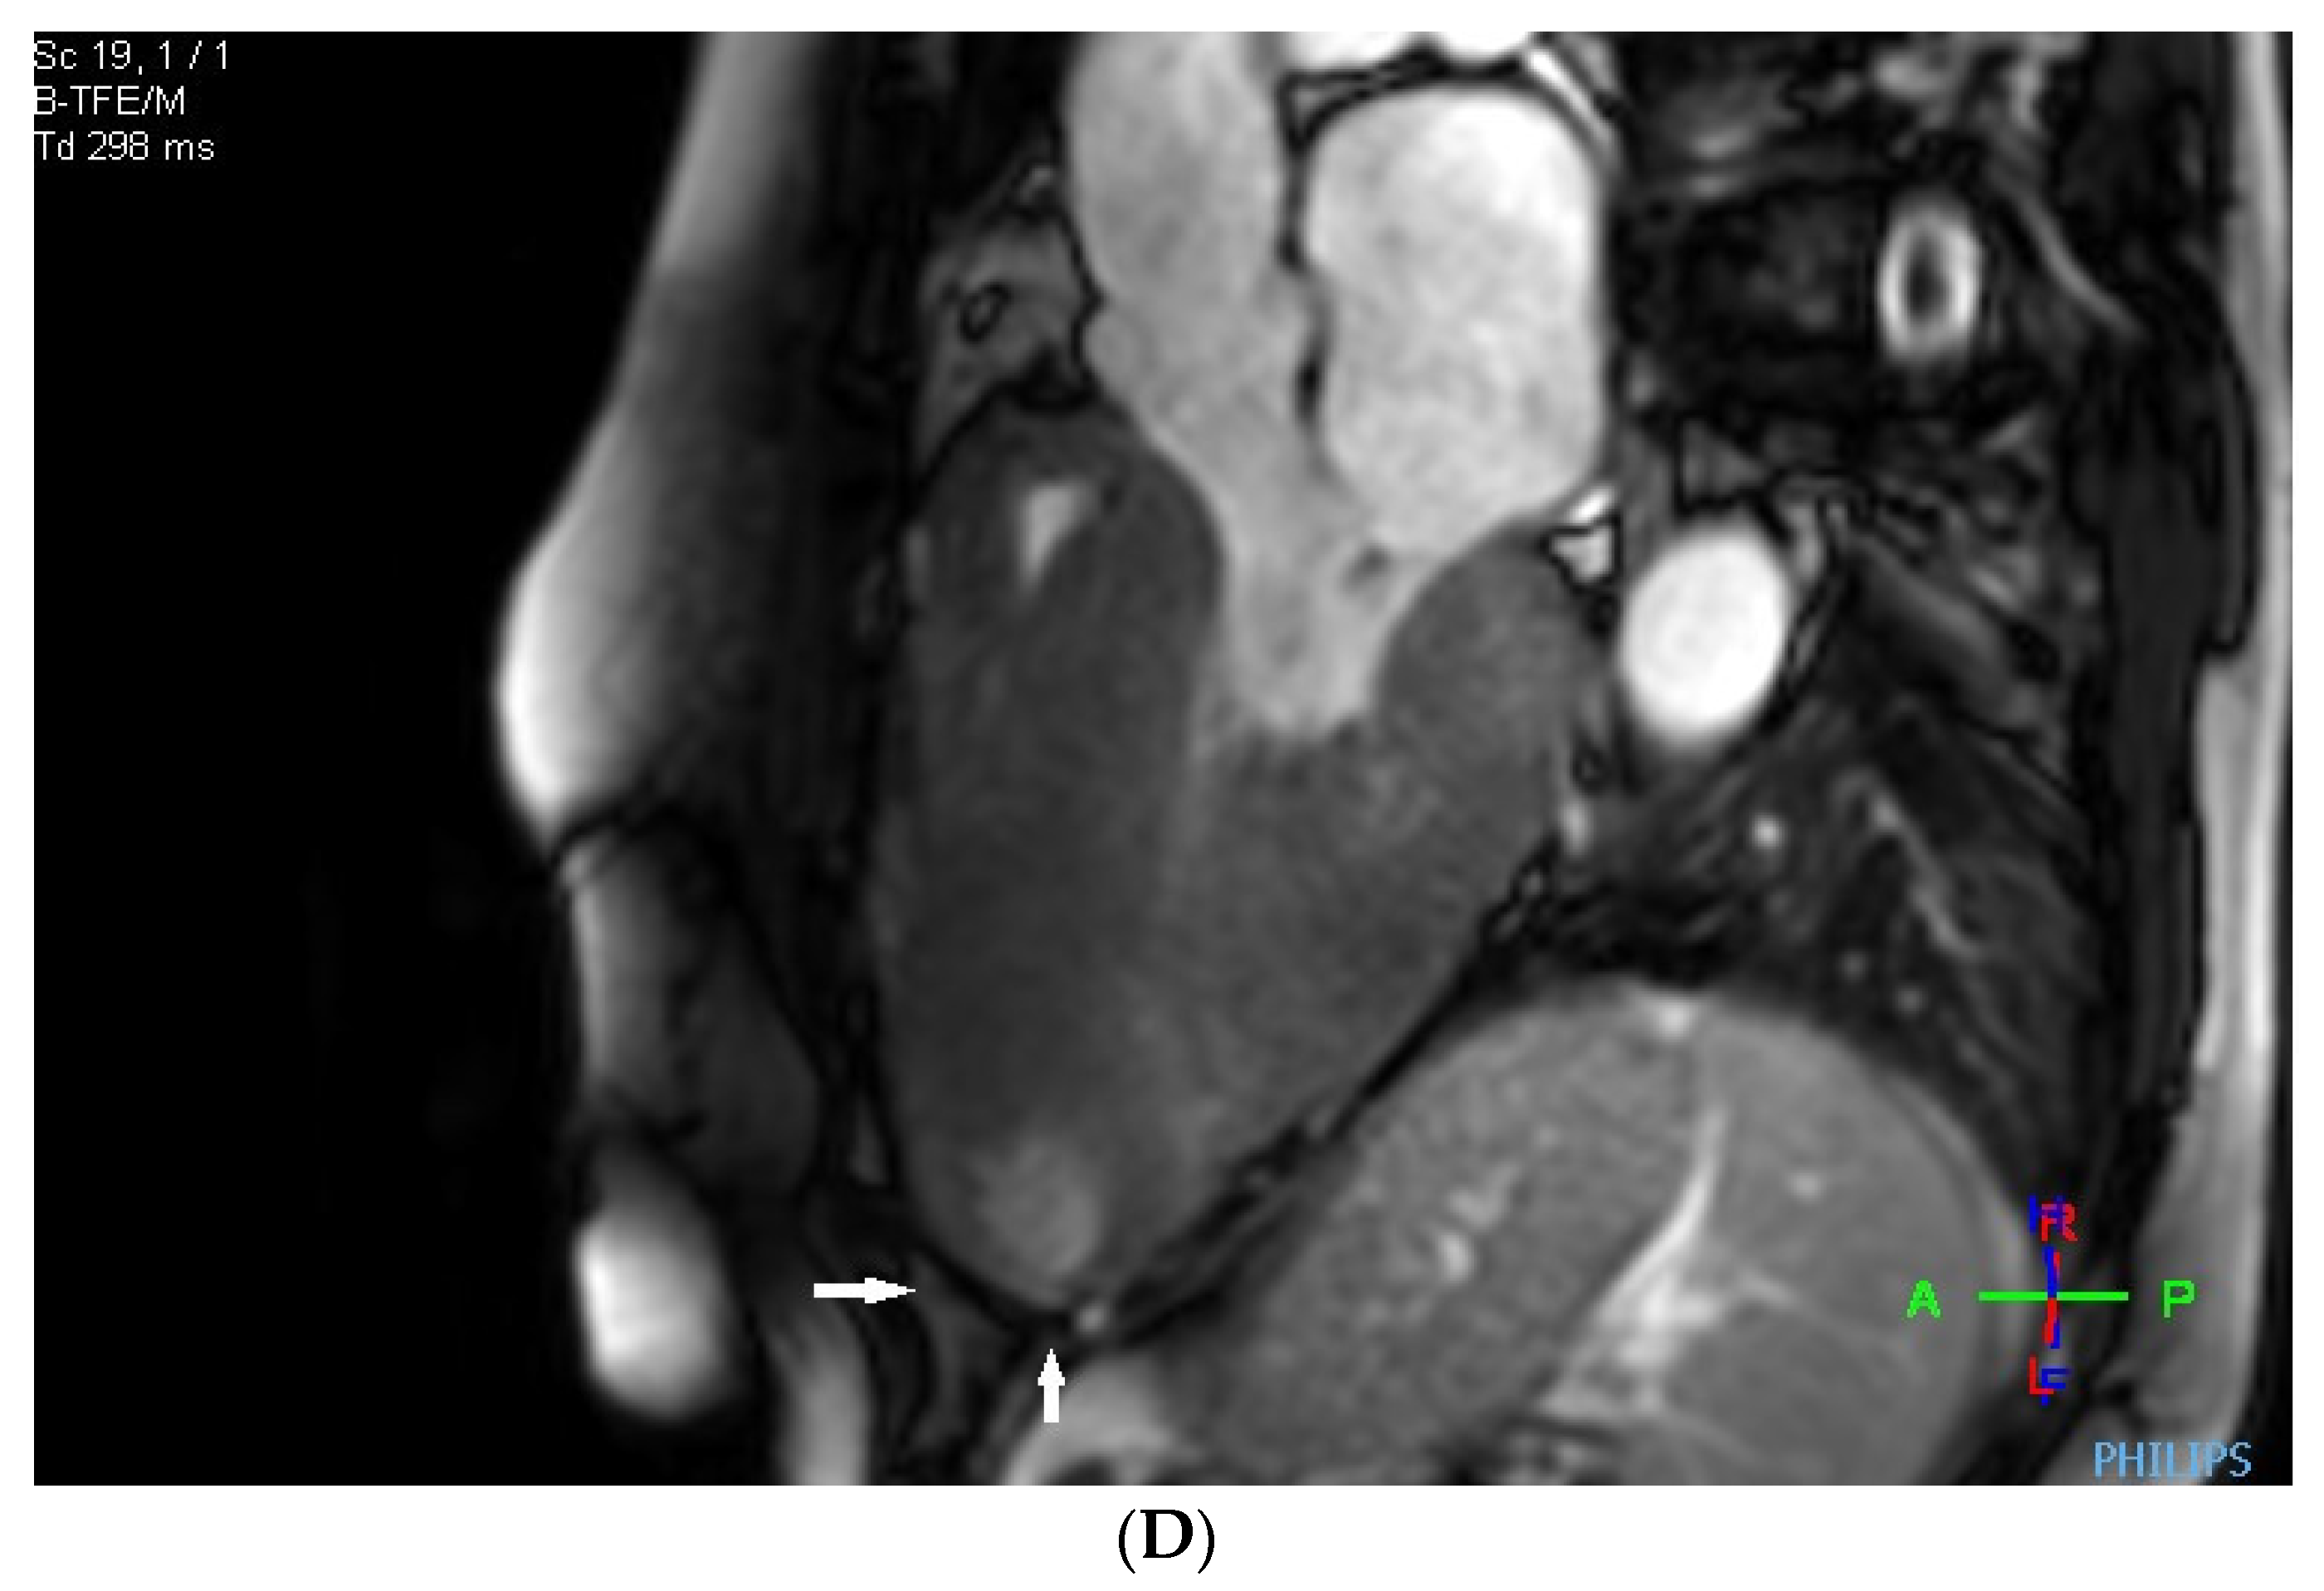

2. Case Description